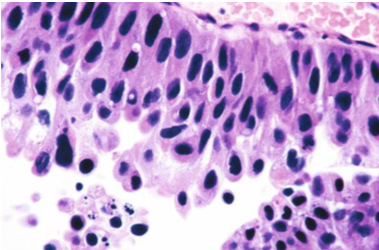

![]() |

| Carcinoma Papilar de Alto Grado. Muestra obtenida de biopsia de vejiga. Se evidencia un incremento en el ratio núcleo citoplasma e hipercromasia nuclear. |